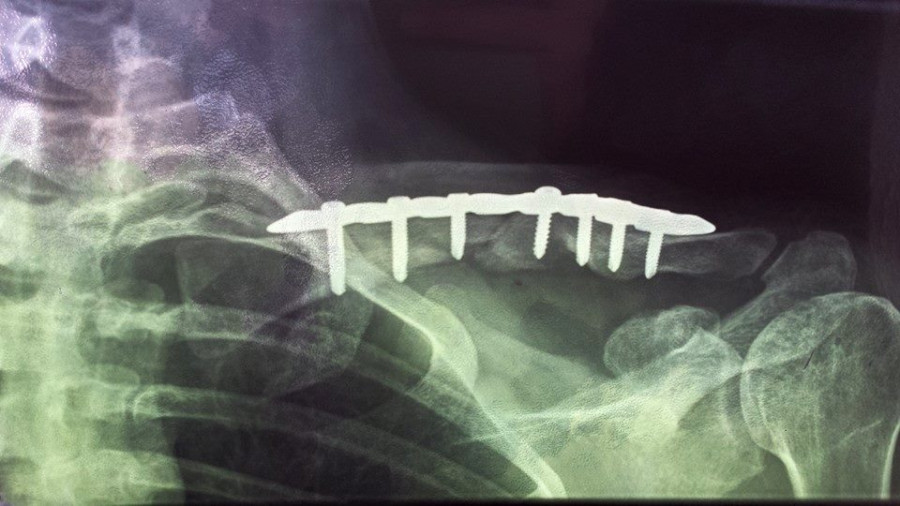

vicky2011 Oui c'est ça, ils n'opèrent que rarement car trop de risques de léser nerveusement voir d'hémorragies importantes (et effectivement 6 ans après je n'ai pas encore retrouvé la même qualité de sensation au niveau de la peau environnante et ai régulièrement des fourmillements très très agaçants vu que c'est un peu une démangeaison fantôme ), ils essaient autant que possible de réparer mécaniquement avec un cal osseux, mais dans mon cas ils ont quand même sérieusement merdé vu que dès le début il était assez flagrant que ça ne pouvait pas revenir en place mécaniquement

Stricto sensu de mémoire j'avais le "droit" de remonter dès les traits de fracture enfin comblés, mais tout en étant avertie qu'une nouvelle grosse chute pouvait faire de considérables dégâts vu que ça ne pêterais pas au niveau de l'osteosynthese mais a côté ... honnêtement j'ai tellement dégusté durant ces quelques mois et surtout avec la greffe osseuse qui s'en est suivie pour combler le bout d'os nécrosé ( du fait des mois d'attente )que je n'avais aucune envie de tenter le diable , je suis remontée au bout de quelques mois mais très occasionnellement, et refroidie , avec gilet airbag (puis projet bébé, puis elevage, donc ça a clairement marqué un tournant dans ma vie equestre , autant je n'avais pas d'appréhension de chuter avant autant désormais ce n'est plus le cas, pourtant sur le coup ça allait, c'est vraiment les mois de galère et douleur qui m'ont un peu "traumatisé"je pense ); je n'ai osé remonter sans airbag qu'une fois les broches retirées